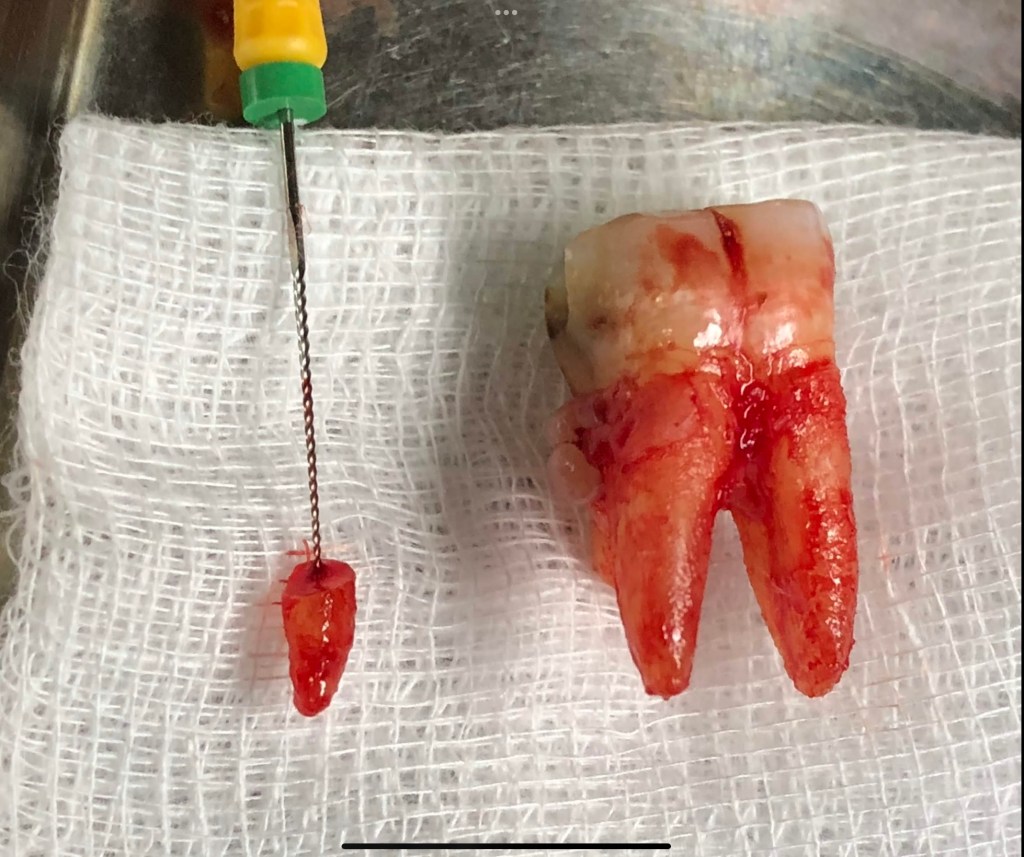

Don’t Remove. (before X-ray) radix-ento พบได้ในคนไทย 12.7% Germination X-ray ช่วยให้เห็นสิ่งที่ซ่อนอยู่ภายใน สังเกต furcation ก็รู้ว่าฟัน Perio Mermaid Premolar ให้สังเกตที่ mouth mirror เห็นถึงความฝ้ามัว เป็น Br พม่าครับ alloy ไม่แข็งมาก X-ray เท่านั้นจึงจะรื้อได้ ผมจะชอบวัดความยาวของฟันบ่อยๆ เทียบกับความยาวในใจที่เดาเอาไว้ RCT incomplete ใครสังเกตเห็นความผิดปกติบ้างครับ? ถึงกับต้องถ่ายทุกมุมเลยซี่นี้ remove ฟัน Crowding เป็น PVC ล้อมด้วยฟัน RCT อย่าลืม X-ray ก่อนถอนนะครับ Share this: Share on X (Opens in new window) X Share on Facebook (Opens in new window) Facebook Like Loading... Uncategorized